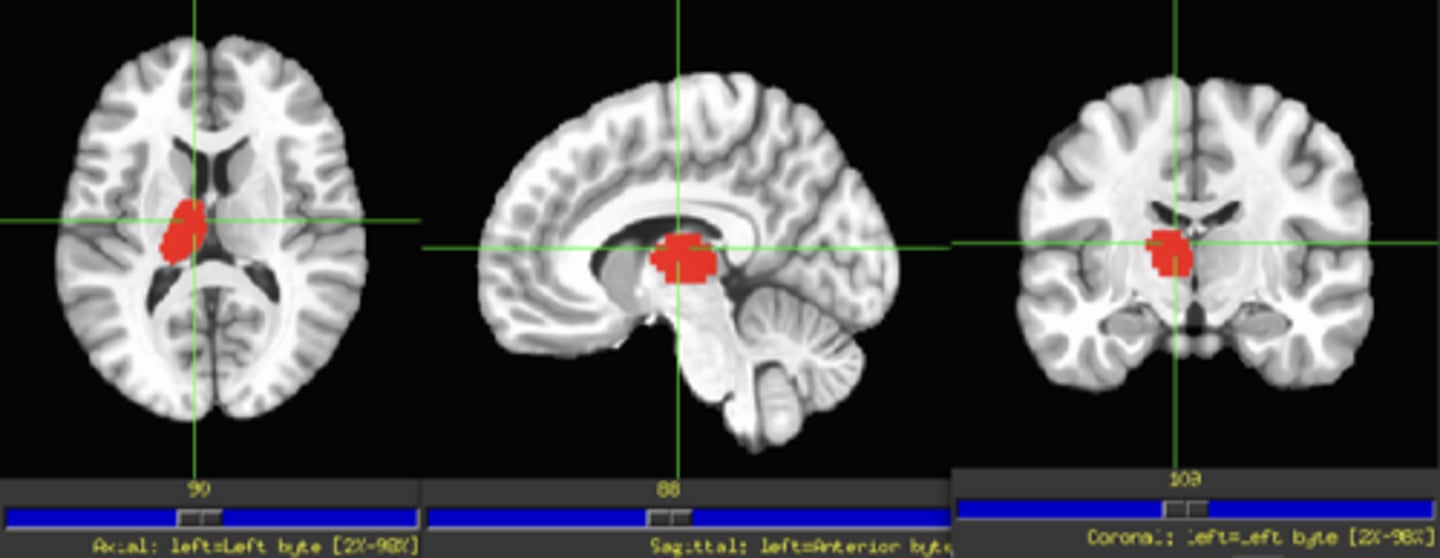

Nigrostriatal Pathway

SN ←> Bg-S

Substantia Nigra

Nucleus Accumbens